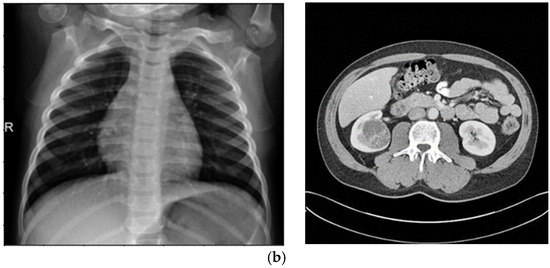

Enhancing Medical Image Segmentation and Classification Using a Fuzzy-Driven Method

Automated analysis for tumor segmentation and illness classification is hampered by the noise, low contrast, and ambiguity that are common in medical pictures. This work introduces a new 12-step fuzzy-based improvement pipeline that uses fuzzy entropy, fuzzy standard deviation, and histogram spread functions [...] Read more.

Automated analysis for tumor segmentation and illness classification is hampered by the noise, low contrast, and ambiguity that are common in medical pictures. This work introduces a new 12-step fuzzy-based improvement pipeline that uses fuzzy entropy, fuzzy standard deviation, and histogram spread functions to enhance picture quality in CT, MRI, and X-ray modalities. The pipeline produces three improved versions per dataset, lowering BRISQUE scores from 28.8 to 21.7 (KiTS19), 30.3 to 23.4 (BraTS2020), and 26.8 to 22.1 (Chest X-ray). It is tested on KiTS19 (CT) for kidney tumor segmentation, BraTS2020 (MRI) for brain tumor segmentation, and Chest X-ray Pneumonia for classification. A Concatenated CNN (CCNN) uses the improved datasets to achieve a Dice coefficient of 99.60% (KiTS19, +2.40% over baseline), segmentation accuracy of 0.983 (KiTS19) and 0.981 (BraTS2020) versus 0.959 and 0.943 (CLAHE), and classification accuracy of 0.974 (Chest X-ray) versus 0.917 (CLAHE). A classic CNN is trained on original and CLAHE-filtered datasets. These outcomes demonstrate how well the pipeline works to improve image quality and increase segmentation/classification accuracy, offering a foundation for clinical diagnostics that is both scalable and interpretable. Full article